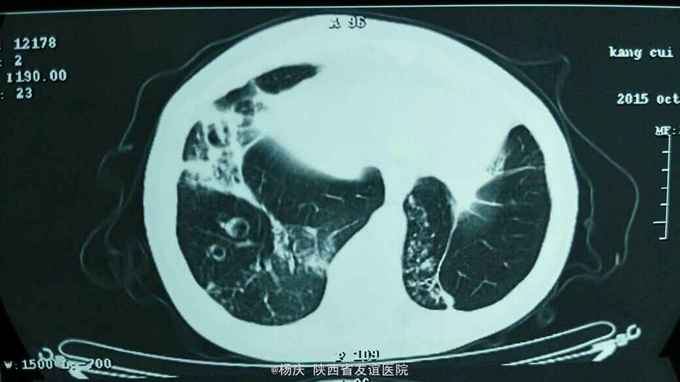

咳嗽,咳痰40年,加重1周,发热1天 40年前始反复咳嗽,咳痰,间断咯血,无声嘶、消瘦。反复多次影像学检查诊断:支气管扩张。1周前上述症状再次发作,外院静脉输液"克林霉素"常规量5天,疗效不佳。1天前出现发热,体温40.0摄氏度,发热前无发冷寒战。今被收住我院,自发病来,精神尚可,大小便正常。 既往无特殊疾病史。

TPR:39.0 80 20。血压120/80mmHg。口唇紫绀,桶状胸,双肺扣呈过轻音,双肺密集湿性啰音。心腹查体无异常。双下肢不肿。

支气管扩张并感染